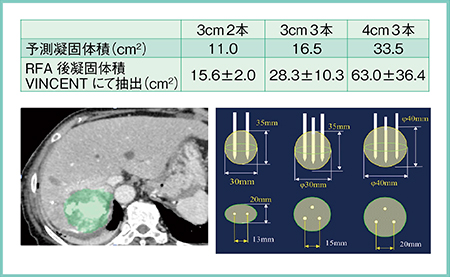

2014年5月〜2015年4月に当院でRFAを施行した206症例304結節のうち,3D Sim-NavigatorとバイポーラRFAシステムを使用し複数本穿刺を行った25症例27結節(平均腫瘍径26.1±10.8mm)を対象に,実際の凝固体積を検証した。2cm針2本,3cm針2本,4cm針2本,3cm針3本,4cm針3本での焼灼体積を,それぞれワークステーション(富士フイルム社製SYNAPSE VINCENT)を用いて抽出し測定したところ,実際の焼灼体積はドジメトリテーブルの予測凝固体積を大きく上回っていた(図6)。

図6 3D Sim-Navigatorを用いたバイポーラRFAの凝固体積